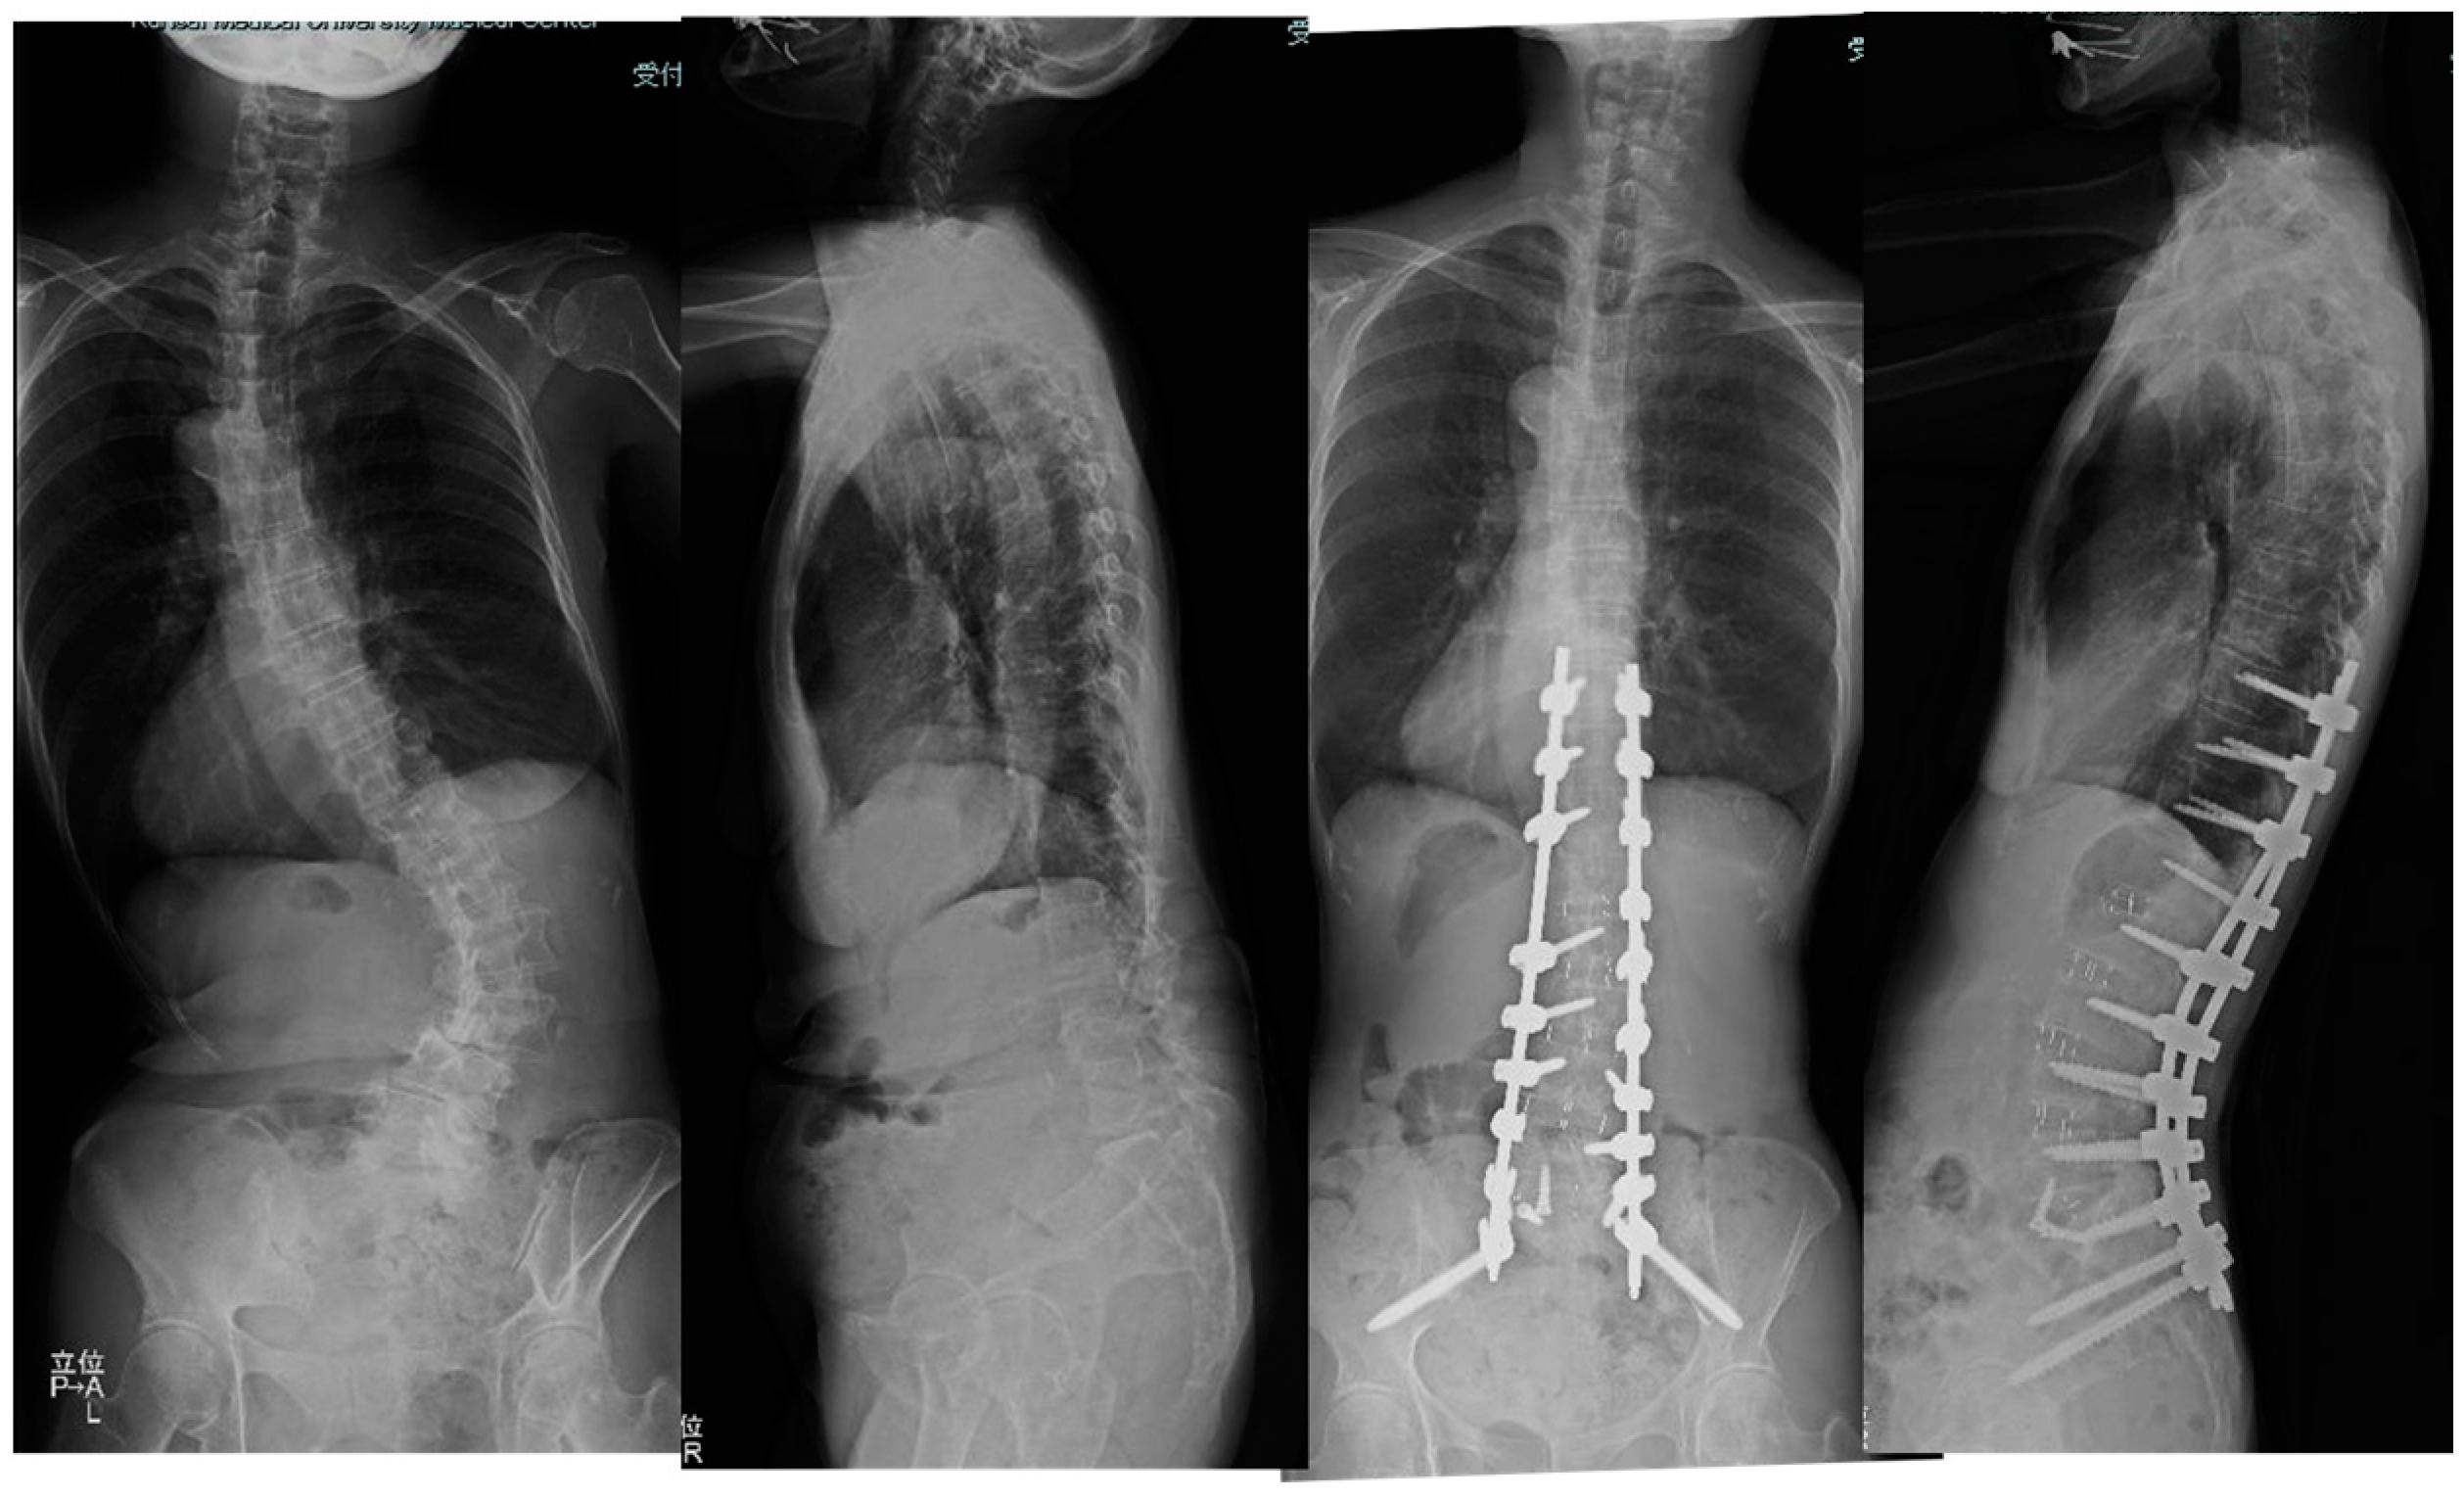

3.1.1. Case 1: 78 Years Old, Female, Degenerative Lumbar Scoliosis